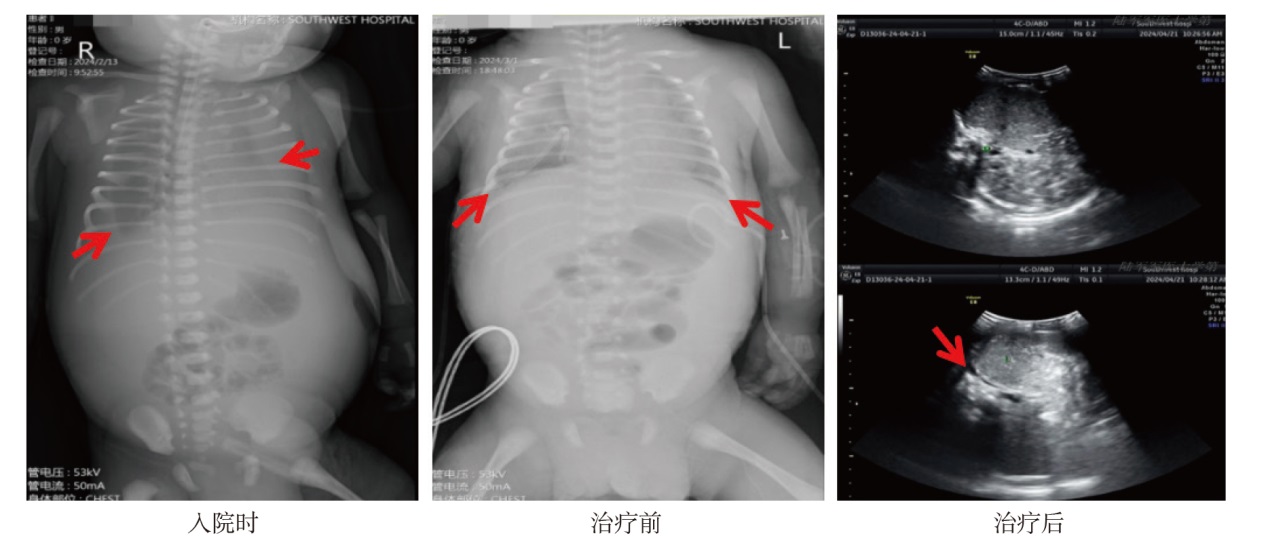

ZHENG Ruixue, SUN Xiaodong, WU Guilan, SHEN Leilei. Neonatal refractory congenital chylothorax: two case reports and literature review[J].Journal of Clinical Pediatrics, 2025, 43(10): 775-781.